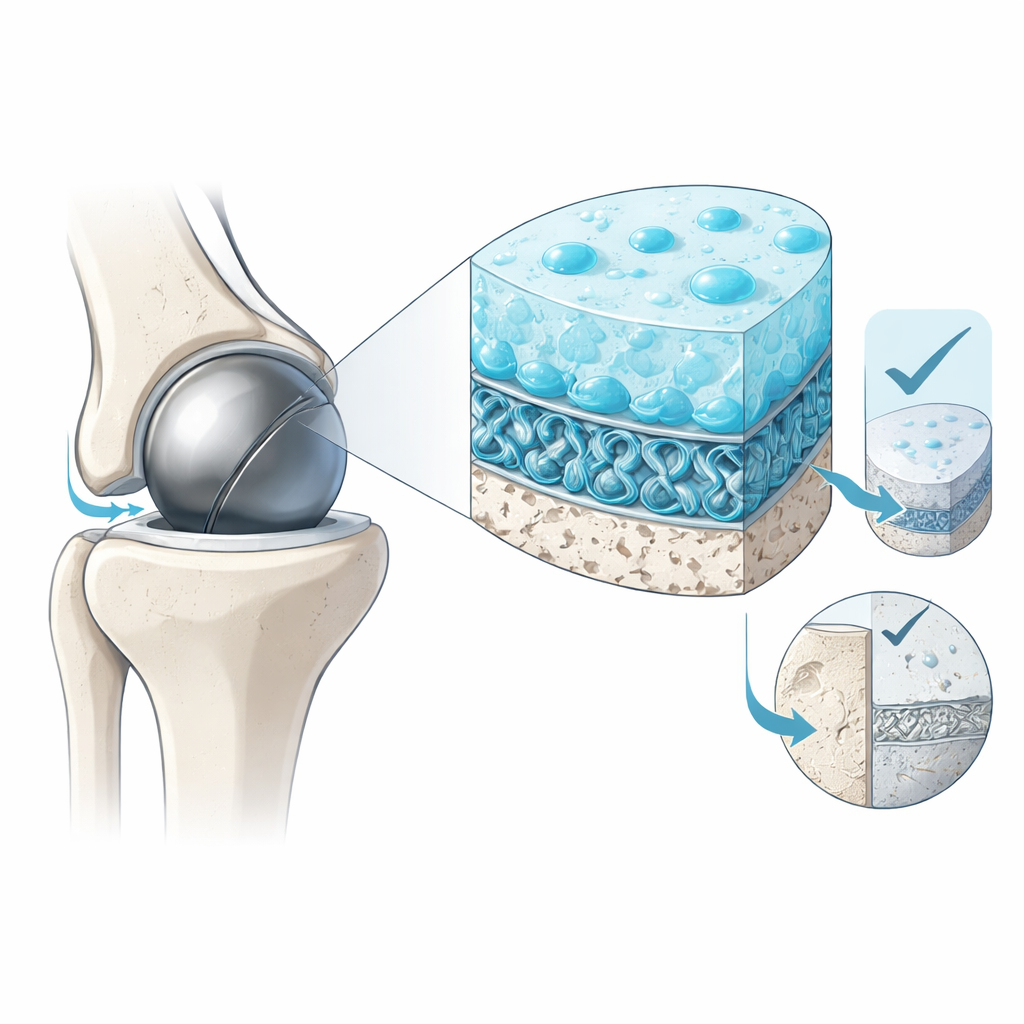

I ricercatori hanno affrontato questo conflitto copiando l’architettura a strati della cartilagine naturale. Nelle articolazioni, una sottile superficie gelificata fornisce lubrificazione, mentre una regione più profonda rinforzata da fibre di collagene sopporta il carico. Il loro rivestimento idrogel con fibre picot (PFHC) riflette questa idea. In cima c’è uno strato superficiale sciolto e poroso che assorbe acqua e forma una sottile pellicola fluida, permettendo alle superfici di scorrere con resistenza minima. Sotto si trova un nucleo più spesso costituito da una rete polimerica densa rinforzata da fibre microscopiche speciali. In fondo, questo nucleo si innesta saldamente su una base plastica porosa in modo che il rivestimento non si stacchi durante i movimenti ripetuti.

Rimanere scivolosi sotto movimenti articolari realistici